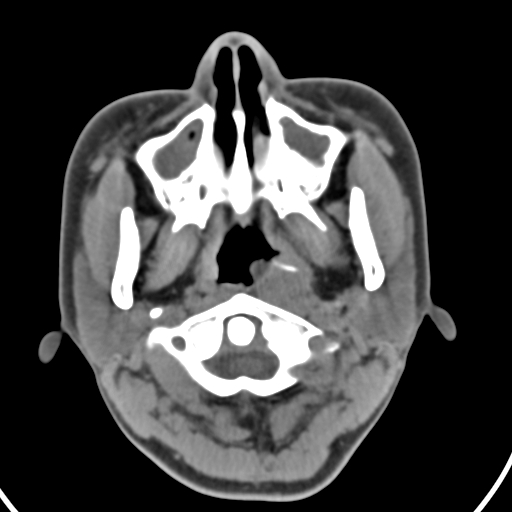

以下是引用zjzjr在2008-12-5 11:46:00的发言:[br]脂肪密度,壁有钙化.考虑口咽部皮样囊肿可能性大.双侧上颌窦炎,双侧下鼻甲粘膜肥厚.增殖腺肥大,扁桃体亦增大,考虑炎性.

以下是引用随光逐影在2008-12-5 18:27:00的发言:[br]1)考虑左侧茎突过长综合征并茎突舌骨韧带囊肿形成突入咽部;左侧咽部慢性炎症。2)鼻咽腺样体肥大。3)双侧扁桃体肿大。4)双侧上颌窦炎。5)双侧下鼻甲粘膜肥厚。